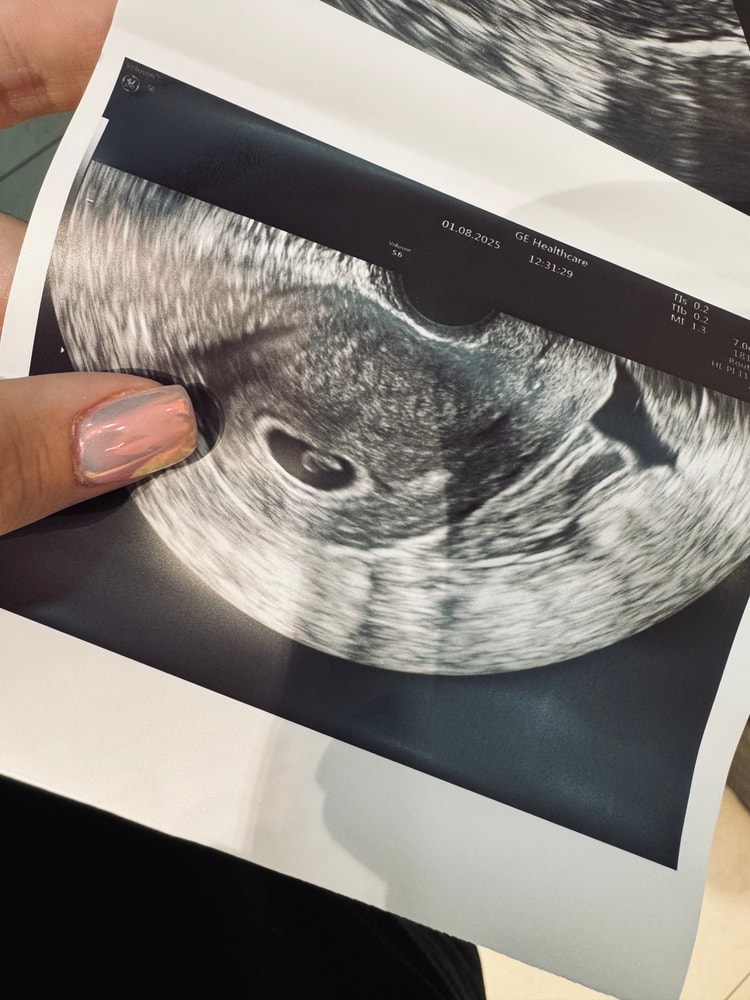

УЗИ 6,6. СБ+

Была на повторном узи. Срок по месячным 6,6. Эмбрион теперь визуализируется, ктр 4,4 (соответствует 6,1). Малюсенькие мы совсем еще, но овуляция была позже на 2-3 дня, поэтому не паникую 🙏🏻 Дорастем 💪🏻 Сердечко не включали, но показали мерцание на экране 🥹